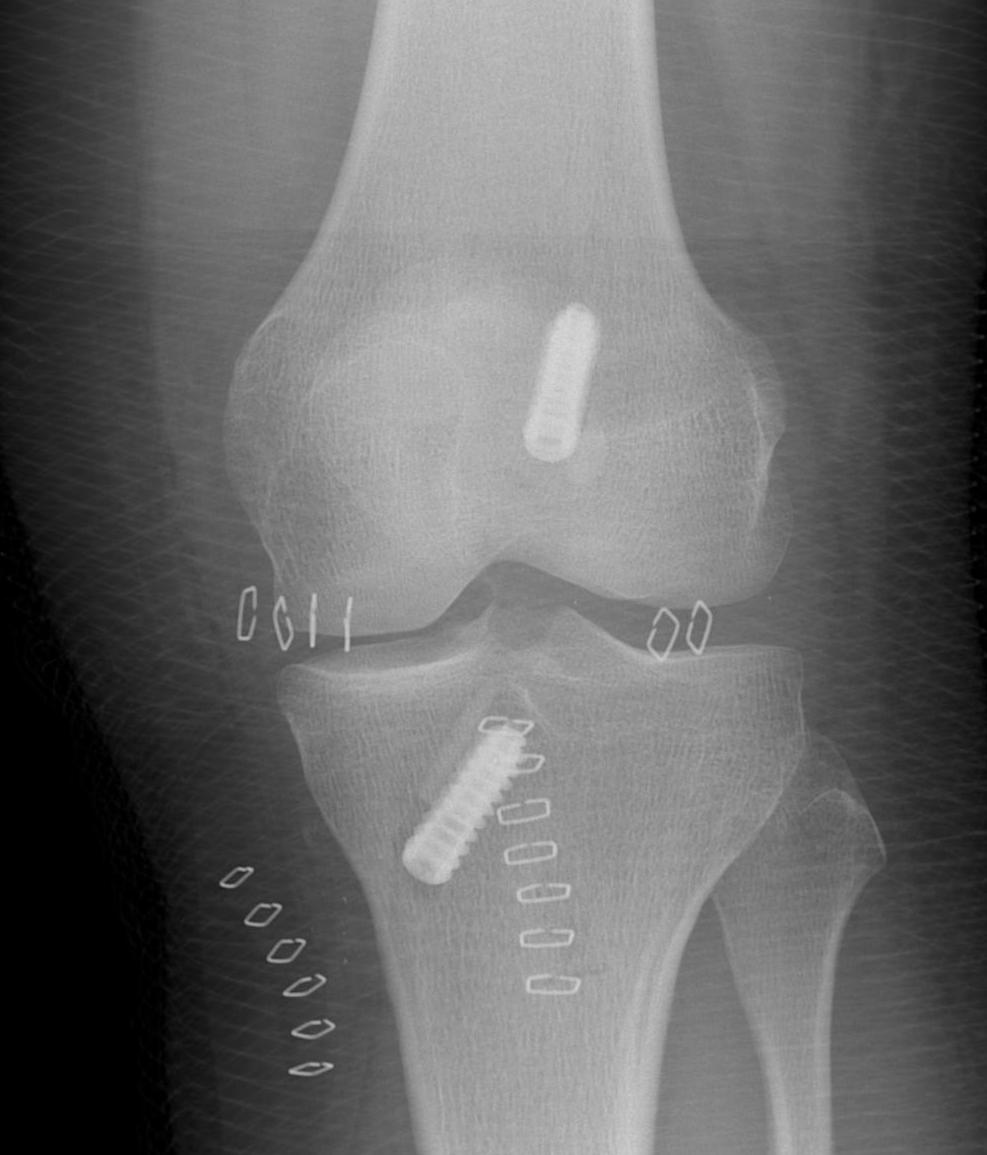

Post Op xrays